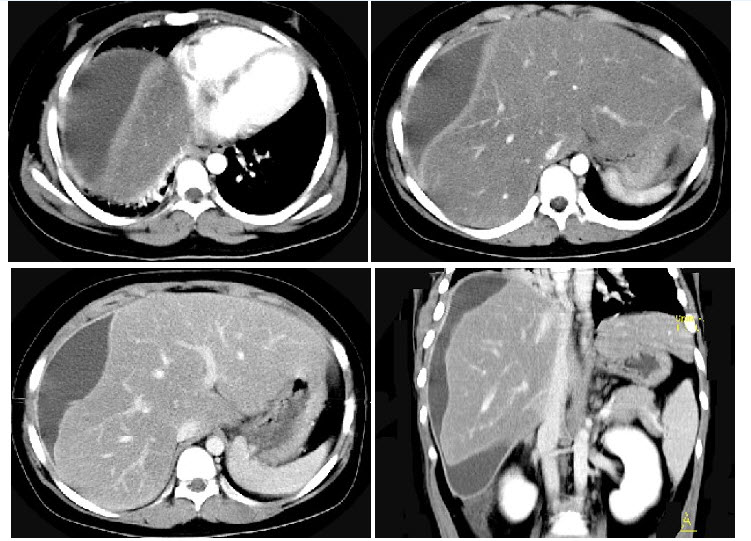

14、单项选择题

男,48岁,胃癌术后1年,未化疗,CT检查如图所示,最可能的诊断为()

A.肿瘤形态不规则

D.动静脉畸形

男,72岁,右上腹痛1月,AFP阴性,无乙肝病史,CT扫描如图,最可能的诊断是()

A.肝脓肿

C.T=1时,表明入射光全部被吸收

D.T=1时,表明入射光全部通过照片

A.小儿及青年多见

B.80%为囊性